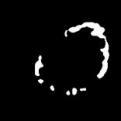

To better retain the deep features of an image and solve the sparsity problem of the end-to-end segmentation model, we propose a new deep convolutional network model for medical image pixel segmentation, called MC-Net. The core of this network model consists of four parts, namely, an encoder network, a multiple max-pooling integration module, a cross multiscale deconvolution decoder network and a pixel-level classification layer. In the network structure of the encoder, we use multiscale convolution instead of the traditional single-channel convolution. The multiple max-pooling integration module first integrates the output features of each submodule of the encoder network and reduces the number of parameters by convolution using a kernel size of 1. At the same time, each max-pooling layer (the pooling size of each layer is different) is spliced after each convolution to achieve the translation invariance of the feature maps of each submodule. We use the output feature maps from the multiple max-pooling integration module as the input of the decoder network; the multiscale convolution of each submodule in the decoder network is cross-fused with the feature maps generated by the corresponding multiscale convolution in the encoder network. Using the above feature map processing methods solves the sparsity problem after the max-pooling layer-generating matrix and enhances the robustness of the classification. We compare our proposed model with the well-known Fully Convolutional Networks for Semantic Segmentation (FCNs), DecovNet, PSPNet, U-net, SgeNet and other state-of-the-art segmentation networks such as HyperDenseNet, MS-Dual, Espnetv2, Denseaspp using one binary Kaggle 2018 data science bowl dataset and two multiclass dataset and obtain encouraging experimental results.